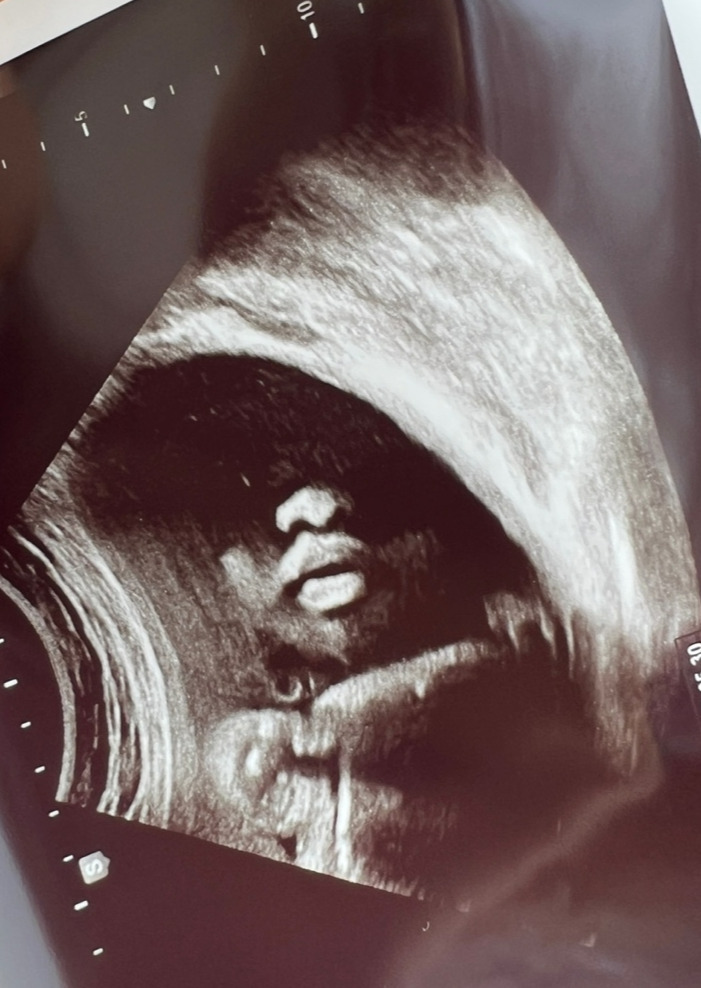

오늘자 통통한 입술의 우리 아기. 조금 사진 무섭게 나왔지만..ㅋㅋㅋ 입술이 너무 귀엽다. 1.5kg 달성!